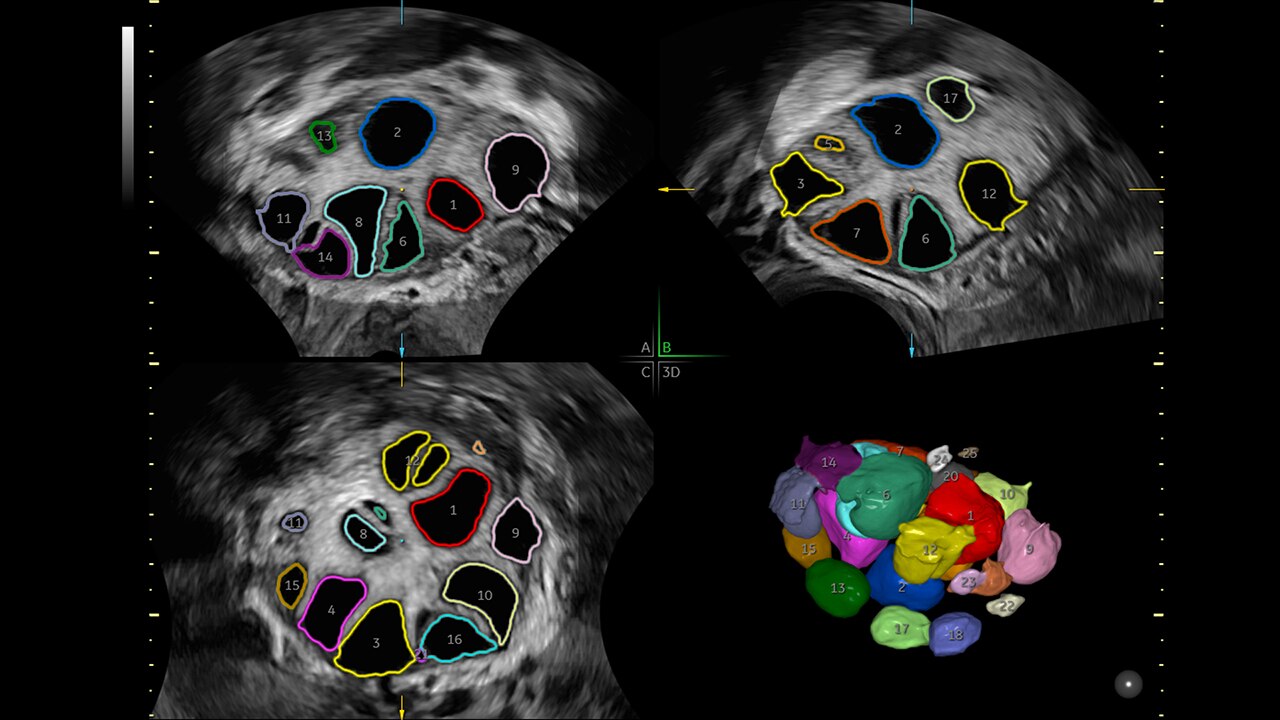

Identify fibroids 88% of the time with Fibroid Mapping